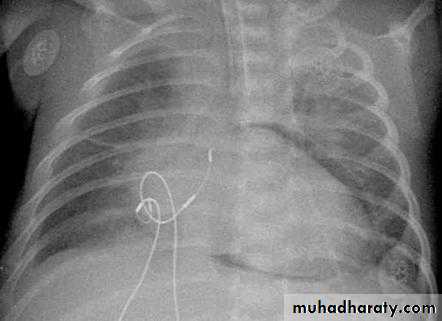

• Check up chest x-ray